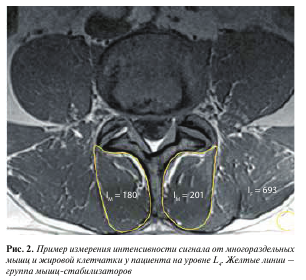

Изображения, полученные с помощью вышеописанной последовательности T1-vibe без жироподавления, открывали в программе InobitecPro в режиме мультипланарной реконструкции, где строились аксиальные срезы, параллельные в коронарной и сагиттальной проекциях нижним замыкательным пластинкам L3-, L4-, Ь5-позвонков (рис. 1). На построенных изображениях на всех 3 уровнях с помощью инструмента «ROI полигон» обводили многораздельные мышцы с обеих сторон, как показано на рис. 2 (вдоль границы остистого и суставного отростков, затем по фасции многораздельной мышцы), для оценки средней интенсивности сигнала и площади выделенной зоны. Кроме того, в режиме T1-vibe без жироподавления с помощью инструмента «ROI овал» измеряли среднюю интенсивность сигнала в жировой клетчатке слева от паравертебральных мышц (см. рис. 2).

Для объективизации полученных данных о наличии жировой ткани в структуре мышц нами был разработан и применен индекс жирового замещения (index of fat replacement, IFR): IFR = IM/IF, где IM — средняя интенсивность сигнала от зоны, соответствующей многораздельной мышце, IF — интенсивность сигнала в жировой клетчатке слева от паравертебральных мышц.